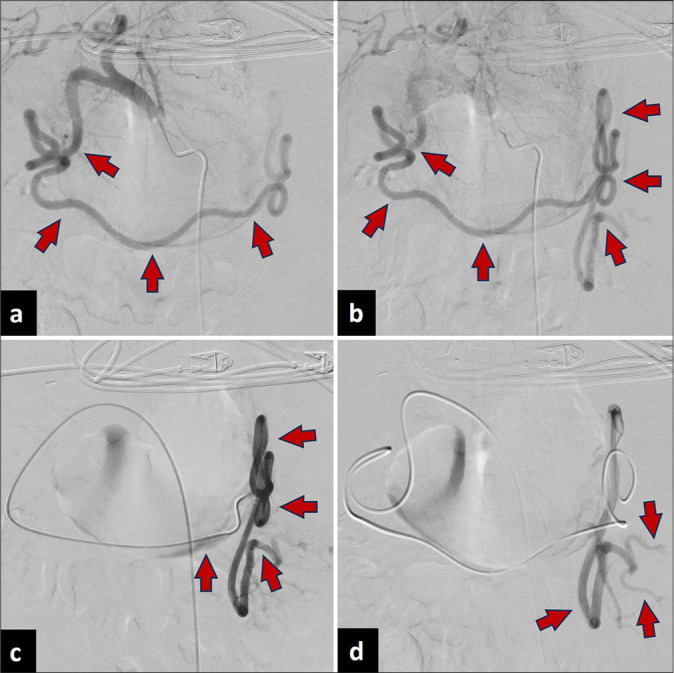

The spleen is a highly vascular organ susceptible to injury in blunt abdominal trauma, often leading to massive blood loss. Splenic artery embolization (SAE) has been shown to be a safe and effective nonoperative approach in cases of hemodynamically stable patients with blunt splenic trauma. SAE can be performed proximally or distally, with both approaches demonstrating similar clinical efficacy. This case report describes emergent splenic embolization for acute abdominal trauma in a liver transplant recipient. However, due to the presence of prior splenic artery ligation, a uniquely alternative route through the gastroepiploic artery was used to gain access to the spleen for embolization.

Abstract Image